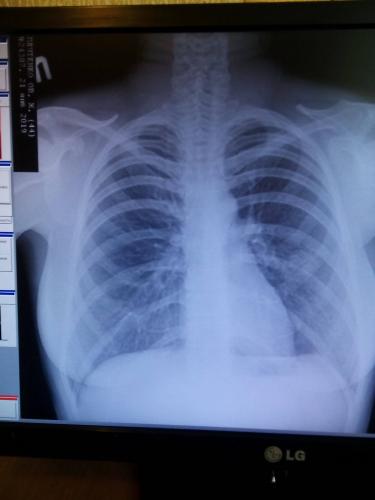

Помимо внешнего осмотра, сбора анамнеза, в том числе жалоб пациента, рентгенологического исследования легких, общего и клинического анализа крови, особое значение для подбора эффективной терапии имеют исследования, связанные с определением возбудителя болезни.

Почему после пневмонии держится температура 37°С? Обычно температура после прохождения полного курса лечения — это вполне нормально явление, если клинический анализ крови и показатели рентгена легких в норме.

Сначала врач ознакомится с жалобами больного, проведет осмотр пациента, оценит состояние его носоглотки. В обязательном порядке требуется проведение флюорографии. Пациенту необходимо сдать кровь и мочу на анализы. Кроме того, исследуется мокрота больного на микрофлору, что дает возможность определить ее характер. Ну и, конечно, следует проверить температурные показатели пациента. После того как будут получены результаты исследований, можно получить полную картину болезни и подобрать действенный способ лечения.